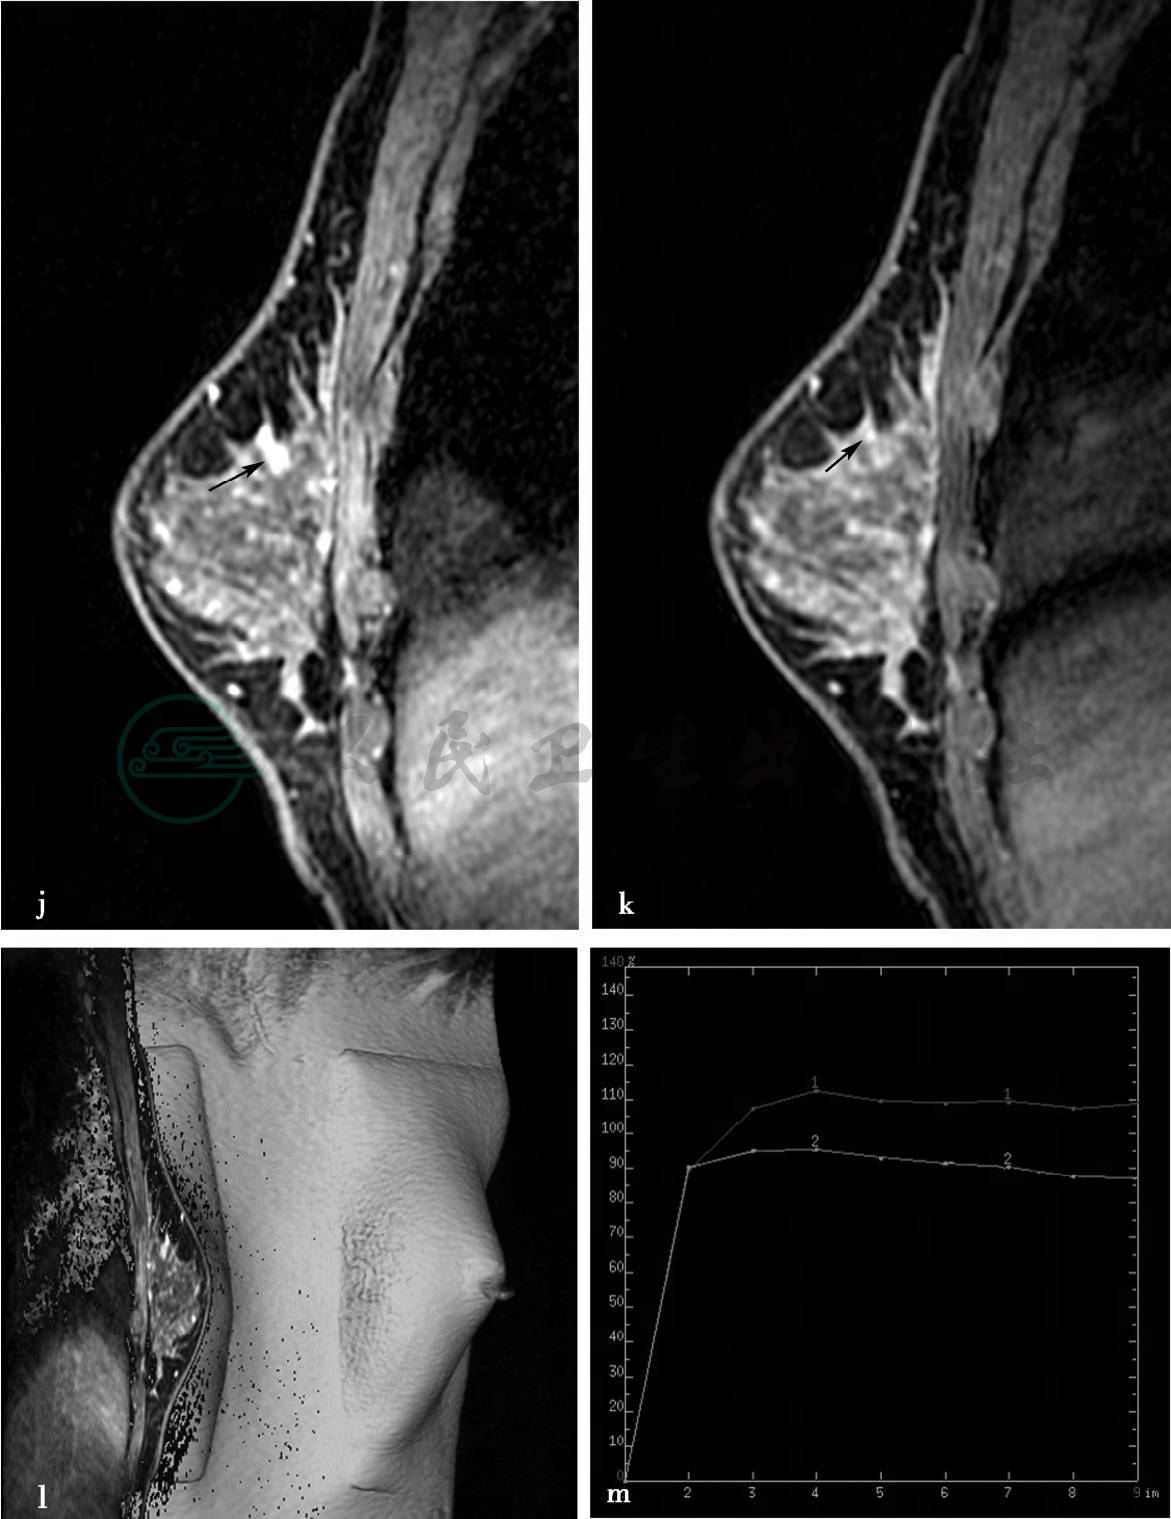

图3 图3h~k,分别为MRI动态增强前及增强后1min、2min、8min。图3l,MRI容积重建(VR)图(见文后彩图)。图3m,病变时间-信号强度曲线图。图3h~k,MRI显示右乳稍内上方(相当于X线片成簇钙化区域)局限异常强化病变,范围约2.8cm×2.3cm× 1.6cm。图3m,多点测量时间-信号强度曲线呈平台型和轻度流出型